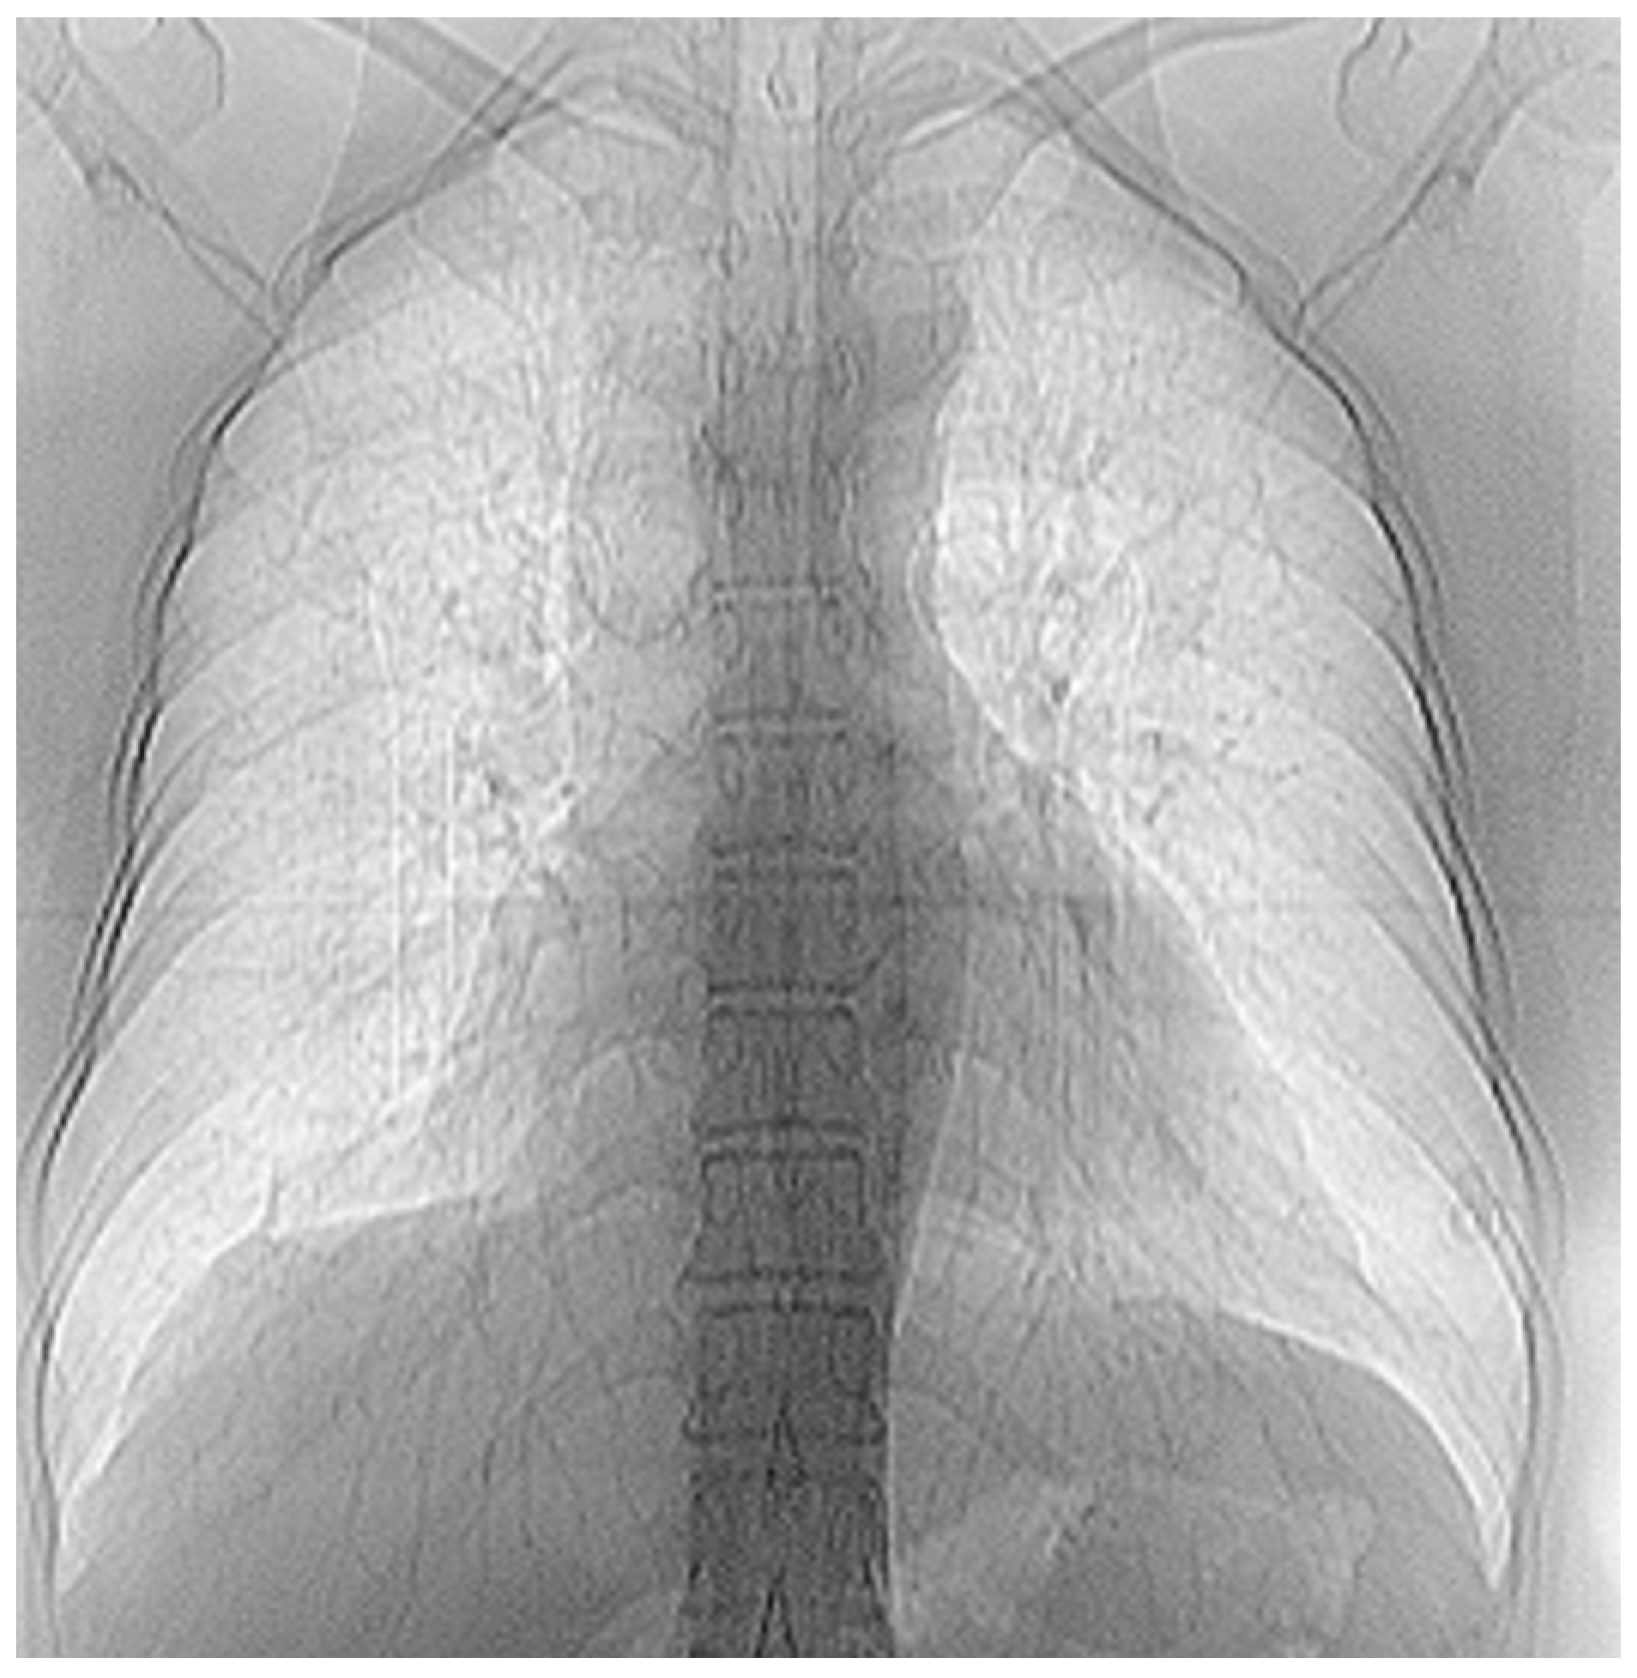

3.7. Results of Healthy Patients—A Final Comparison Using Control Data

In this subsection, we present and discuss the pulmonary CT scan of healthy lungs, which were not affected by the presence of SARS-CoV-2.

The chest radiograph of healthy lungs on which the fractal analysis was performed is shown in Figure 29a. Aside from the high-quality imaging provided by CT procedures (Figure 29a,b), the picture evaluation assured quantitative information regarding various structural features, such as the fractal dimension and lacunarity.

Figure 30 shows the 2D box-counting algorithm with the local fractal dimension calculation for the healthy-lung CT image. Figure 31 displays the 3D graphical representation of the voxels present in the CT lung image of healthy patient. Table 7 presents the calculated values for the fractal dimension and the lacunarity of the CT image evaluations for the healthy patient.

Table 7 shows the known fractal indicators, such as the fractal dimension of the CT image of the left lung, dHL = 1.6410 ± 0.3577, and lacunarity Λ = 0.0475; and the fractal dimension of the right lung, dHR = 1.6318 ± 0.3598, and lacunarity, Λ = 0.0486.

Figure 29. (a) Healthy lung image, (b) binary version, (c) mask for the left lung, (d) mask for the right lung.